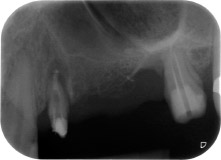

Fig. 1: Paziente di 58 anni. La radiografia preoperatoria mostra una lesione periodontale apicale in corrispondenza del dente 24 e una perdita orizzontale di tessuto osseo alveolare nel secondo quadrante.

Una paziente donna di 58 anni lamentava dolore e aumentata mobilità del dente di appoggio del ponte 24. Era presente infiammazione periodontale con tasche di profondità di 7 mm a livello mesiobuccale e di più di 12 mm a livello distale, nonché coinvolgimento di terzo grado della forcazione. Inoltre, la radiografia rivelava una lesione periodontale estensiva attorno alla regione apicale del dente pretrattato 24 (in altro luogo) a livello endodontico (Fig. 1).

Un anno più tardi, sono stati estratti i denti 25 e 26 in seguito a trauma e per motivi endoperiodontali, prima del posizionamento del ponte. Era stata diagnosticata una lesione endoperiodontale combinata in corrispondenza del dente 24, di eziologia incerta. La paziente desiderava conservare i denti 24 e 27 di appoggio al ponte e non accettava una protesi rimovibile finale, o temporanea. Si è pertanto deciso di fare il possibile per conservare entrambi i denti, nonostante la prognosi negativa basata sugli esiti clinici e radiologici.

Tutto il tessuto osseo vestibolare e distale era mancante in corrispondenza della radice buccale. La possibilità di attacco era essenzialmente ristretta alla radice palatale, evidenziando la prognosi negativa preliminare. Anche il dente 27 mostrava un punto di attacco orizzontale ridotto e una rarefazione apicale minima (cfr. Fig. 1), senza sintomi clinici.